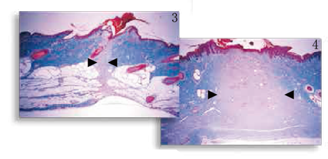

圖3,4

傷口愈合改進(jìn) 觀察豬皮皮膚切口的縮影(圖3 )與標(biāo)準(zhǔn)的尖端切口(圖4 ),經(jīng)由梅森氏三色染色顯示纖維增生明顯減少,如膠原沉積的程度和炎癥反應(yīng)。